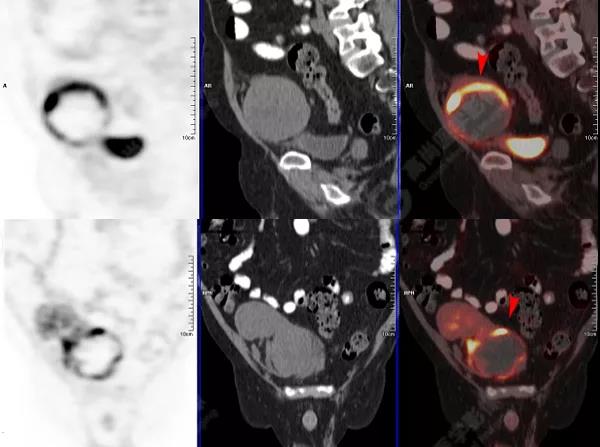

↑移植腎下部等密度腫塊,代謝環(huán)狀增高,SUVmax13.4,中心代謝缺損

移植腎腫物穿刺活檢病理:移植后EBV陽性的彌漫大B細(xì)胞淋巴瘤。